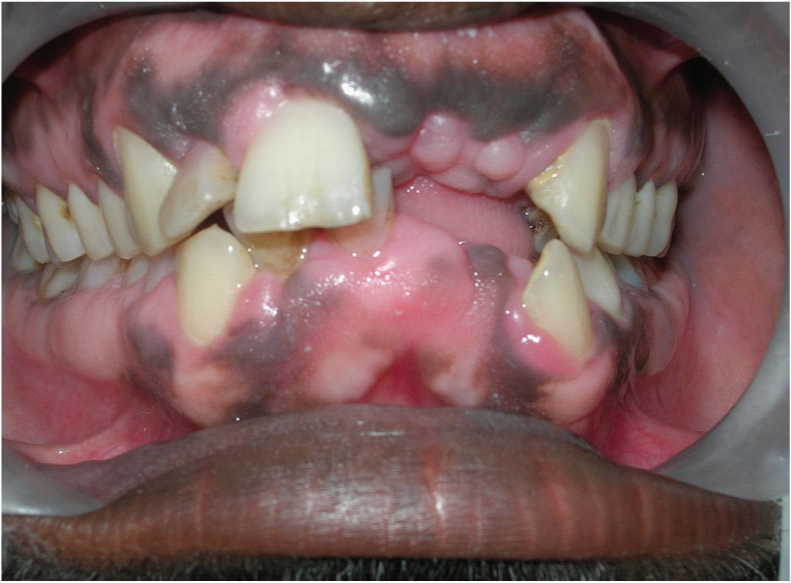

A 28-year-old male patient reported to the Department of Oral Medicine and Radiology, Saveetha University (Chennai, India) with a chief complaint of mobility of teeth in upper and lower jaw and gingival enlargement for past two months. He gave history of loss of front teeth in both jaws and gradual enlargement of gingival since then. [Table/Fig-1] showing the partially edentulous maxilla and mandible along with the gingival enlargement. [Table/Fig-2] showing the extent of mobility of 12.

Showing the partially edentulous maxilla and mandible along with the gingival enlargement

Showing the extent of mobility of 12